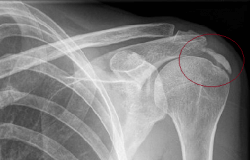

Calcificación en el hombro